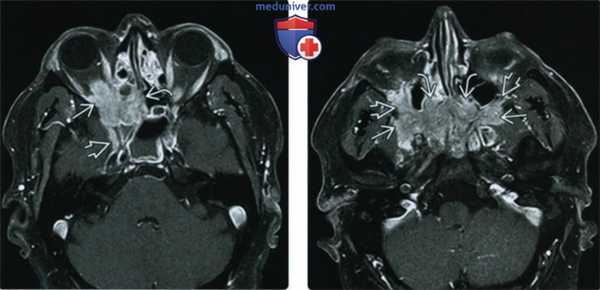

(Слева) При МРТ Т2ВИ FS в аксиальной проекции у этого же пациента определяется инфильтративное идиопатическое воспаление верхушки глазницы, решетчатого лабиринта и круглого отверстия. Гиперинтенсивные обтурированные пазухи легко отличимы от идиопатического воспалительного псевдотумора глазниц/внеглазничной локализации. Гипоинтенсивность обусловлена диффузным фиброзом, часто развивающимся в ткани обширного псевдотумора.

(Справа) При МРТ Т2ВИ FS в аксиальной проекции у этого же пациента определяется обширное внеглазничное идиопатическое воспаление, распространяющееся на крылонебные ямки и заднюю часть полости носа.

(Слева) МРТ, Т2-ВИ, режим подавления сигнала от жира, аксиальный срез: у этого же пациента в области верхушки глазницы, решетчатого синуса и круглого отверстия определяется идиопатический воспалительный инфильтрат. Подвергшиеся обструкции гиперинтенсивные придаточные пазухи носа могут быть легко дифференцированы от ИВГл-ИВВ. Гипоинтенсивные зоны представляют собой диффузный фиброз, который часто наблюдается при более протяженных поражениях.

(Справа) МРТ, Т2-ВИ, режим подавления сигнала от жира, аксиальный срез: у этого же пациента определяется протяженная зона идиопатического воспаления, распространяющаяся на крылонебные ямки и задние отделы полости носа.